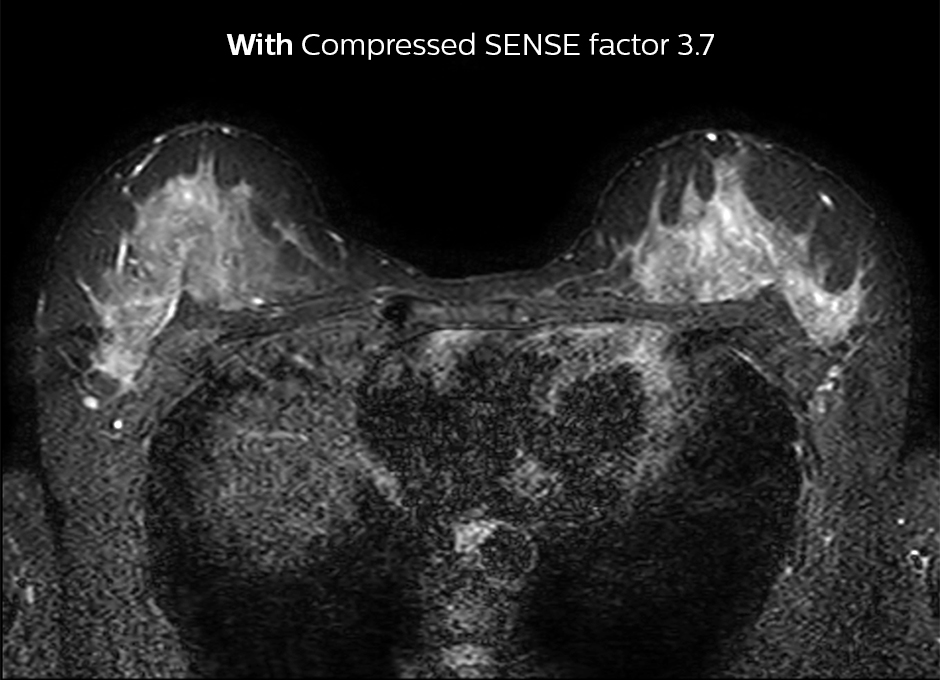

Accelerating 2D breast MRI

Compressed SENSE allows 29% shorter scan time with similar spatial resolution.

2D STIR, scan time 3:39 min, voxel size 1 x 1.25 x 3 mm.

2D STIR, scan time 2:36 min, voxel size 1 x 1.26 x 3 mm.